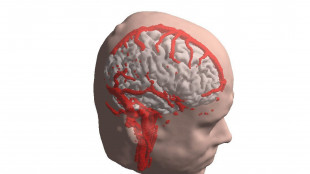

Iperattività e deficit d'attenzione, strumento di Ia per scovare disturbo precocemente

Stima con precisione rischio che un bambino lo sviluppi anni prima di una diagnosi tipica